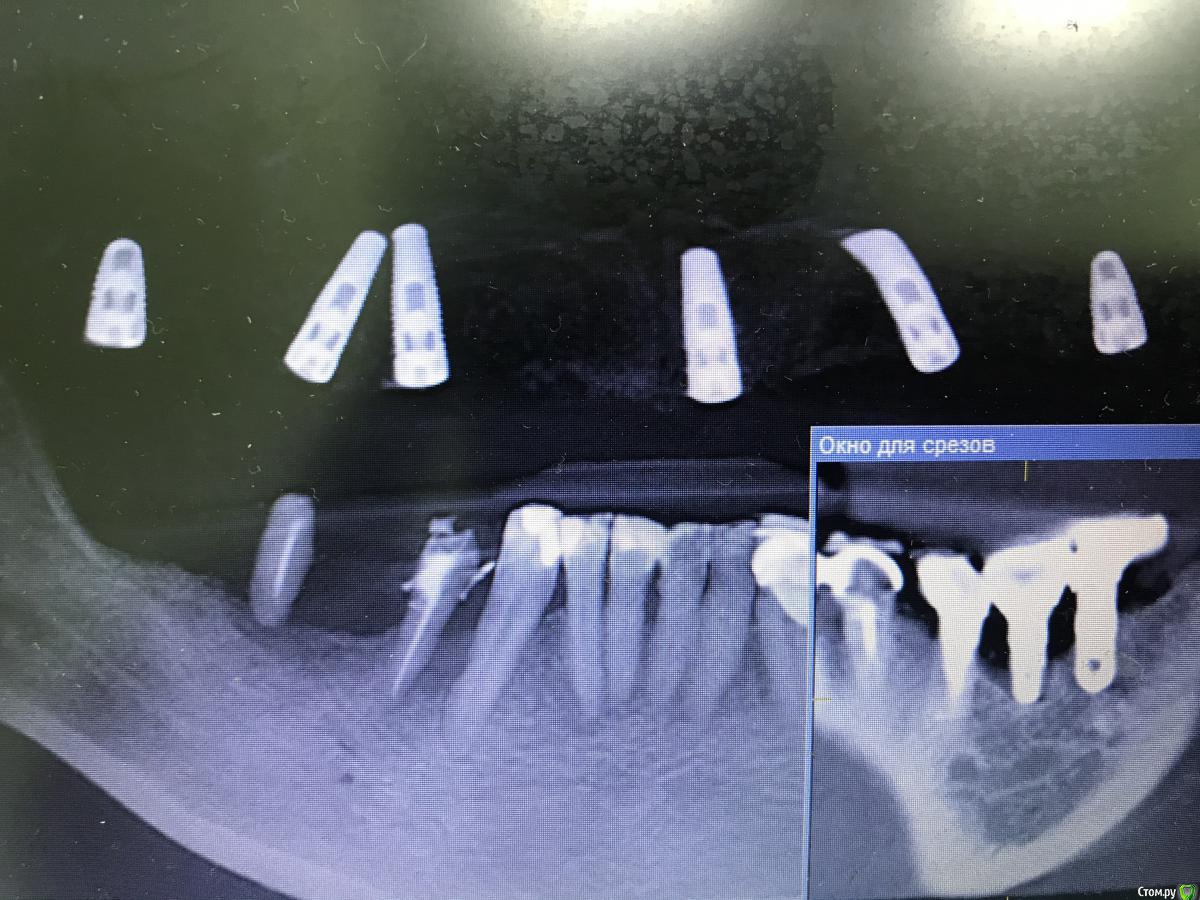

Жадный доктор Опубликовано 21 июля, 2020 Поделиться Опубликовано 21 июля, 2020 (изменено) Доброго всем дня! возникла проблема с имплантатом 36. 35, 36, 37 установлены в другой клинике примерно 8 лет назад. 37 просверлил шахту, выкрутил винт абатмнта. Подошла отвертка с шестигранником 1.25. 35 просверлил также, шестигранник оказался сорванным в хлам. Работа коппом дала небольшой урожай сколотой керамической облицовки. Пришлось убирать имплант вестибулярным доступом. Может у кого есть рецепты приготовления такого блюда? Изменено 21 июля, 2020 пользователем Жадный доктор Ссылка на комментарий

Жадный доктор Опубликовано 21 июля, 2020 Автор Поделиться Опубликовано 21 июля, 2020 (изменено) Удалил периимплантитный, 35,37 пока стоят Изменено 21 июля, 2020 пользователем Жадный доктор Ссылка на комментарий

АнтонТЛТ Опубликовано 21 июля, 2020 Поделиться Опубликовано 21 июля, 2020 Там к оставшимся на нч тоже есть вопросы Ссылка на комментарий

Жадный доктор Опубликовано 21 июля, 2020 Автор Поделиться Опубликовано 21 июля, 2020 Есть наборы для выкручивания повреждённых винтов. Имплантат удалять из-за винта, это жёстко Удалил средний имплантат с периимплантитом, 36, мост с опорой на 35, 37 стоит на месте, он нужен для жевания Ссылка на комментарий